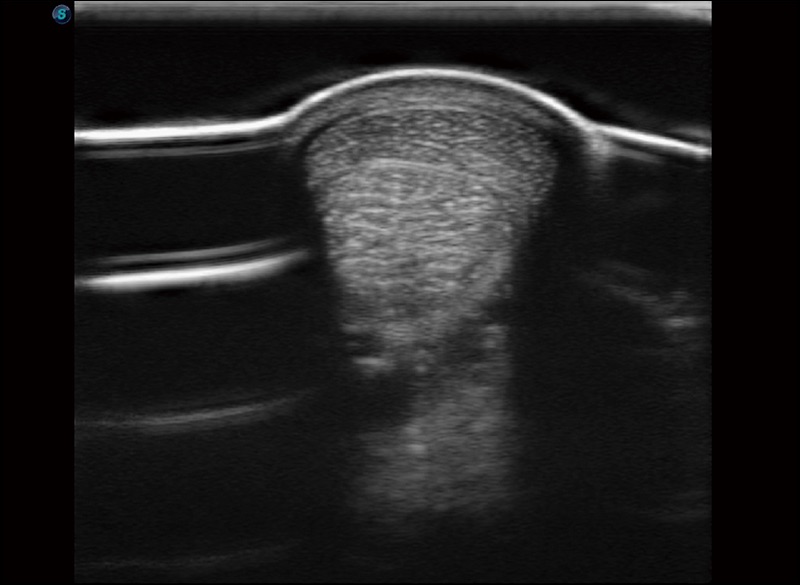

任意波束合成技术

在不牺牲时间分辨率的情况下提供出色的图像